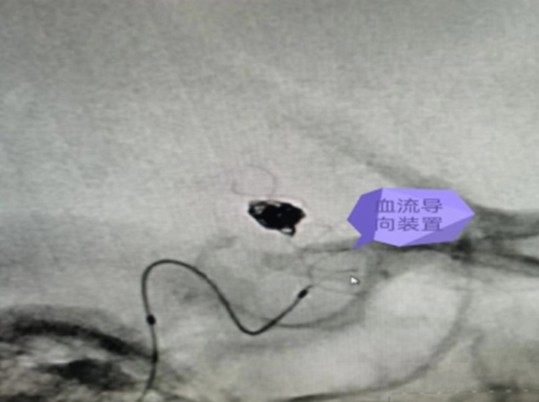

7月14日,在麻醉科及介入手術(shù)室的密切配合下,神經(jīng)外科醫(yī)師團(tuán)隊(duì)順利完成了此例后交通段血泡樣動(dòng)脈瘤血流導(dǎo)向裝置+彈簧圈栓塞手術(shù),拆除了龍女士腦子里的“不定時(shí)炸彈”。

據(jù)悉,顱內(nèi)血流裝置(PED)是一種治療顱內(nèi)復(fù)雜動(dòng)脈瘤新型的治療方式,通過置入所到病變動(dòng)脈后,使動(dòng)脈內(nèi)的血流動(dòng)力學(xué)發(fā)生改變,緩慢的在動(dòng)脈瘤內(nèi)形成血栓,內(nèi)膜上皮攀爬到支架表面從而來修復(fù)病變血管使其發(fā)生血管重建來修復(fù)病變的載瘤動(dòng)脈。血流導(dǎo)向裝置的發(fā)展更新了動(dòng)脈瘤的治療理念,對(duì)顱內(nèi)復(fù)雜動(dòng)脈瘤的治療結(jié)果產(chǎn)生革命性的變化,具有手術(shù)微創(chuàng),操作簡(jiǎn)單,安全性相對(duì)較高,在降低動(dòng)脈瘤復(fù)發(fā)方面更具有優(yōu)勢(shì)。